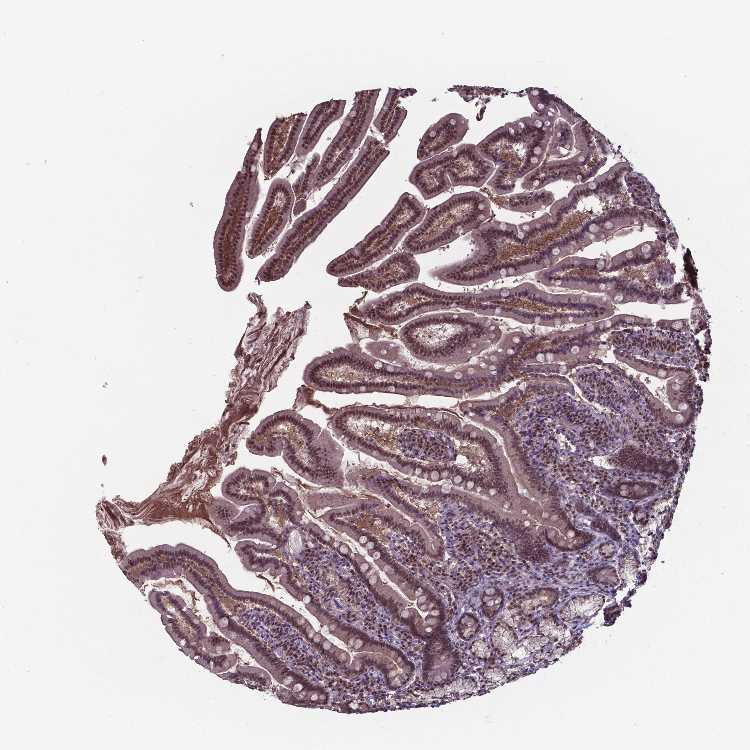

DUODENUM - Antibody stainingi

Antibody staining in the annotated cell types in the current human tissue is reported as not detected, low, medium, or high, based on conventional immunohistochemistry profiling in selected tissues. This score is based on the combination of the staining intensity and fraction of stained cells.

Each image is clickable and will lead to virtual microscopy that enables deeper exploration of all samples and also displays staining intensity scores, fraction scores and subcellular localization as well as patient and tissue information for each sample.

Antibody HPA000289Antibody CAB019435Antibody CAB073410

Glandular cells Not detectedMediumMedium